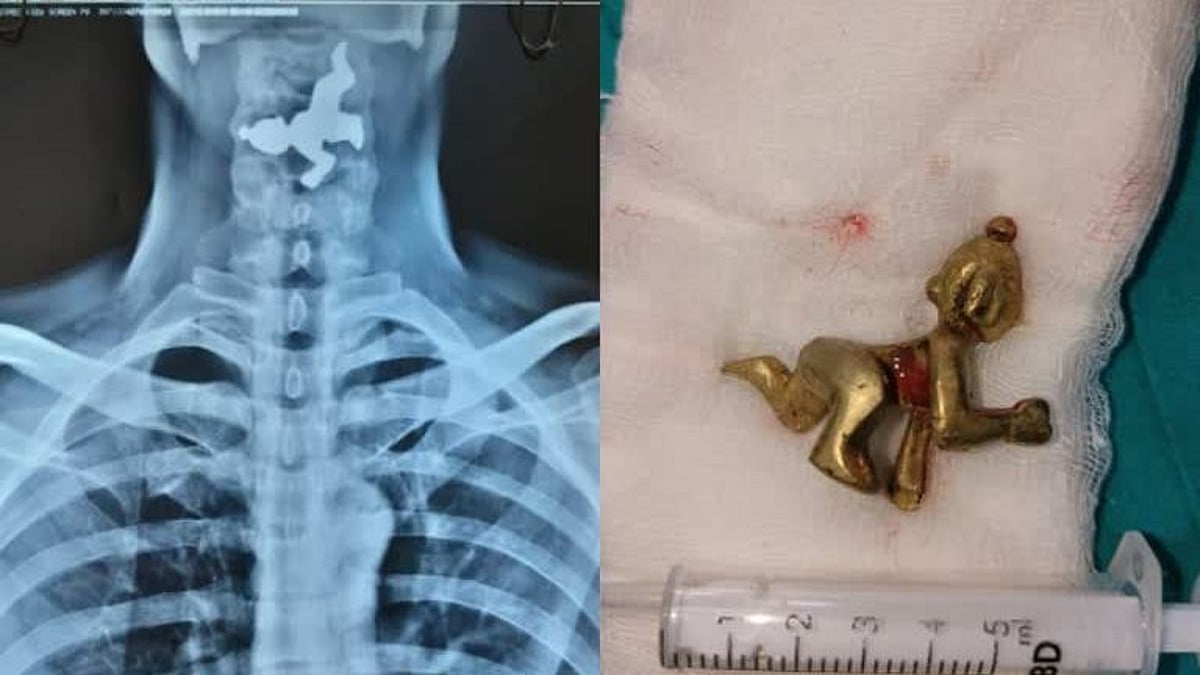

“கடவுள் பக்தியில் புனித நீரோடு சிலையை விழுங்கிய பக்தர்?” :  தொண்டையில் சிக்கிய சிலையால் நடந்த விபரீதம்! 🕑 2022-06-24T07:08

“கடவுள் பக்தியில் புனித நீரோடு சிலையை விழுங்கிய பக்தர்?” : தொண்டையில் சிக்கிய சிலையால் நடந்த விபரீதம்!

இதனையடுத்து, அவருக்கு ENDOSCOPY என்ற சிகிச்சை மூலம் தொண்டையில் சிக்கியிருந்த பொருளை தொண்டை வழியே வெளியே எடுத்தனர். இது குறித்து மருத்துவர்கள்